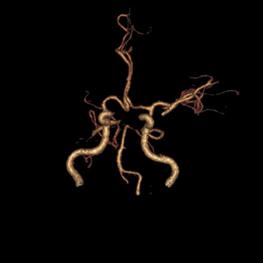

病例38:烟雾病合并右侧大脑前动脉A2段开窗畸形